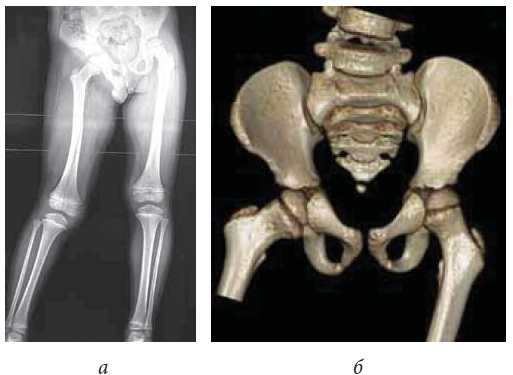

X-ray examination was performed using Digital Diagnost v.2 apparatus and spiral computed tomography (CT) was performed using Philips Brilliance cT apparatus. These examinations indicated changes in the form of pelvic skew, abduction of the right lower limb, and diaphysis deformity of the right femur which indirectly indicated the presence of fibrous cords in the soft tissues of the right thigh (Fig. 2).

Fig. 2. X-ray of the lower limbs in the standing position (a), and CT of hip joints (b) of patient D, aged 6 years, before surgery